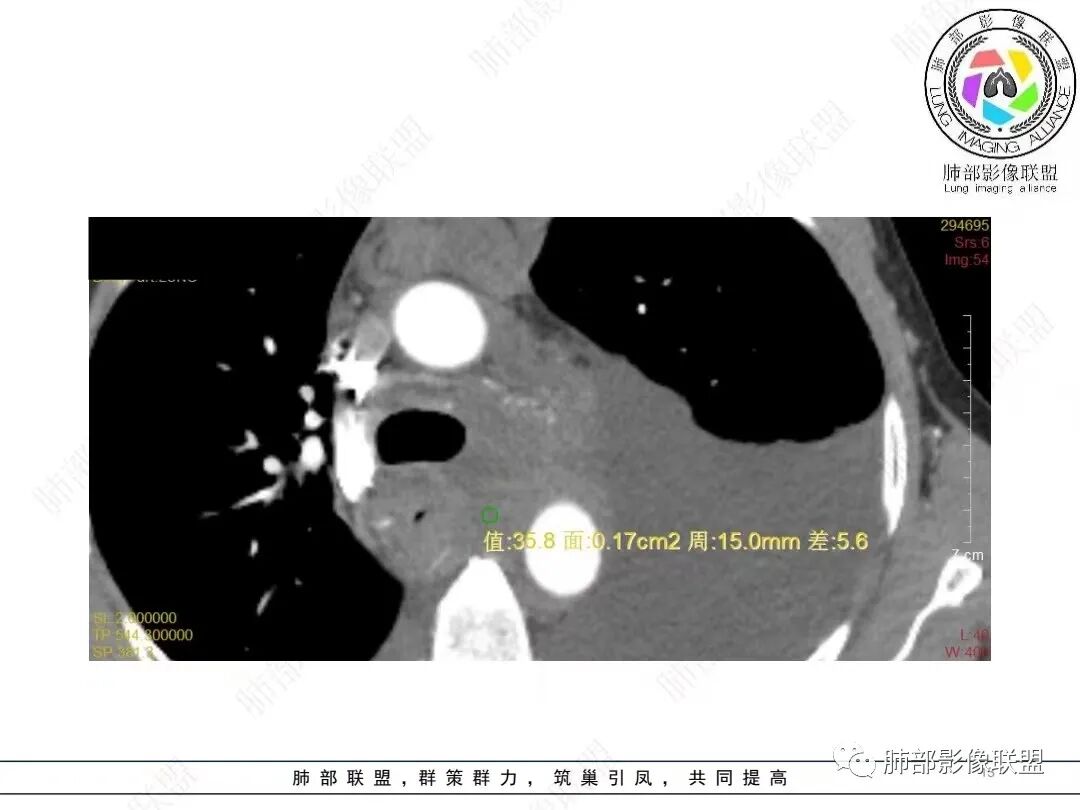

目前的图:主要是胸部的病灶。胸膜弥漫斑块状增厚。强化明显,内部血管漂浮。前纵隔部分病灶强化偏低。

就胸部病灶的特性,好像与甲状腺的不一致。强化、内部的坏死囊变不相符。我认为甲状腺来源的几率不高。

2.影像学特点:病变范围相当广泛,多发块状影累及纵隔、胸膜、前胸壁(胸大肌下)、前上腹壁等。胸膜弥漫性斑状增厚为主,明显强化,纵隔旁椭圆形块影较密实,沿胸膜分布趋势,未见支气管等结构进入。后纵隔块影较大,占位效应明显,肺静脉受累狭窄。双侧胸腔积液。

甲状腺右叶相对低密度结节影,边界清楚,不均匀分隔样强化,经验上分析与胸部病灶缺乏关联性。